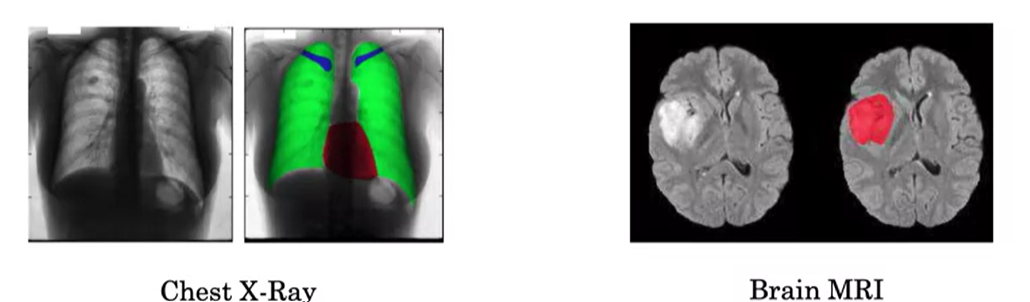

의료 영상에서, 예를 들어 흉부 엑스레이가 주어졌을 때 특정 질환을 진단하고자 할 수 있다. 하지만 의사들에게 더 유용한 것은, 환자의 해부학적 구조에서 특정 부위가 정확히 어디인지 분할(segmentation)할 수 있는 것이다. 왼쪽 이미지에서는 폐, 심장, 그리고 쇄골(즉, 쇄골뼈)이 다른 색상으로 분할되어 있다. 이러한 분할 작업은 비정상적인 부분을 쉽게 찾아내고, 심각한 질병을 진단하며, 수술 계획을 세우는 데 도움을 줄 수 있다. 오른쪽 예시에서는 뇌 MRI 스캔을 사용하여 뇌종양을 감지하고 있다. 수작업으로 종양을 분할하는 작업은 매우 시간이 많이 걸리고 힘든 일이다. 그러나 학습 알고리즘이 종양을 자동으로 분할할 수 있다면, 이는 방사선과 의사의 시간을 많이 절약해 주고, 수술 계획에도 유용한 입력이 될 수 있다. 이 결과를 생성하는 데 사용된 알고리즘은 U-Net 이라는 알고리즘이다.